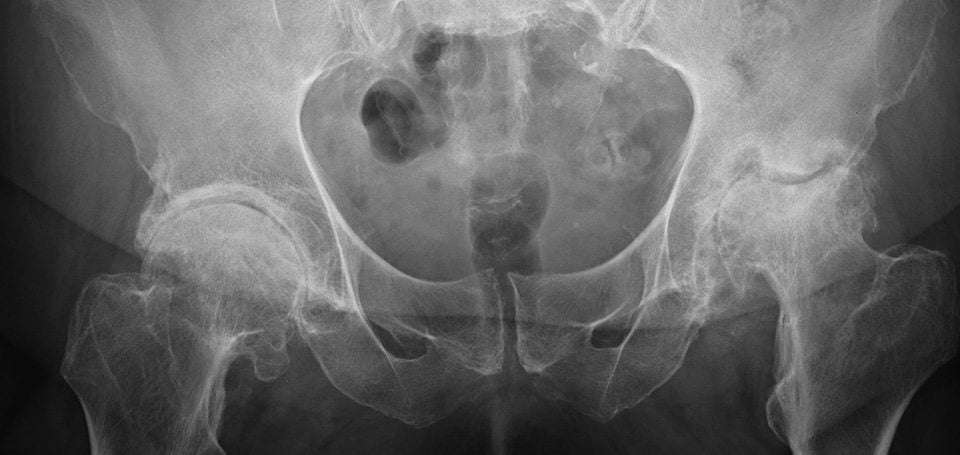

На фоне такой активности или в силу патологий опорно-двигательного аппарата сустав изнашивается, терпит дистрофические изменения. Пациент жалуется на боли, снижается двигательная активность, ухудшается качество жизни. Может случиться и перелом шейки бедра.

Различные патологии ТБС — артроз, коксартроз и другие дегенеративно-дистрофические изменения — носят прогрессирующий характер. Приостановить течение болезни возможно на ранних сроках медикаментозно, но вскоре патология проявится снова, а препараты уже будут бесполезны.

Соединительная ткань сустава не может самовосстанавливаться, регенерировать. Местное воздействие или пероральный прием лекарств становятся пустой тратой времени. Разрушение ТБС будет прогрессировать, вплоть до полной потери больным возможности передвигаться. Остановить процесс реально, но при своевременном обращении к ортопеду.